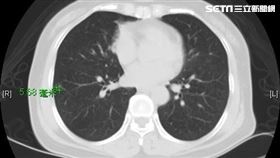

肺結節突增8倍大 患者:洩天機會遭報應

胸腔外科權威暨重症專科醫師李佳穎,日前他在自己的臉書...

幫友擋大劫肺結節突大8倍 醫看了也嚇壞

玄學在科學上雖無法證明,但有時詭異巧合,總讓人不寒而...